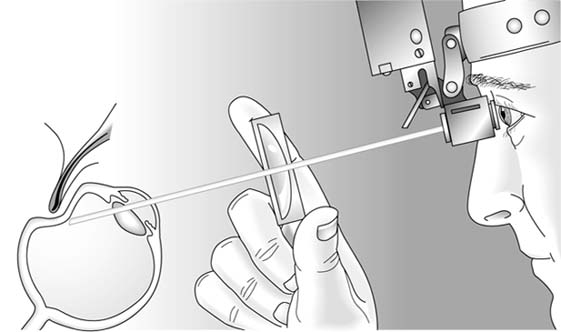

Scleral depression (Figure 2-18) is performed as the peripheral retina is being examined with the indirect ophthalmoscope. A smooth, thin metal probe is used to gently indent the globe externally through the lids at a point just behind the corneoscleral junction (limbus). As this is done, the ora serrata and peripheral retina are pushed internally into the examiner's line of view. By depressing around the entire circumference, the peripheral retina can be viewed in its entirety.

Figure 2-18

Figure 2-18: Diagrammatic representation of indirect ophthalmoscopy with scleral depression to examine the far peripheral retina. Indentation of the sclera through the lids brings the peripheral edge of the retina into visual alignment with the dilated pupil, the hand-held condensing lens, and the head-mounted ophthalmoscope.